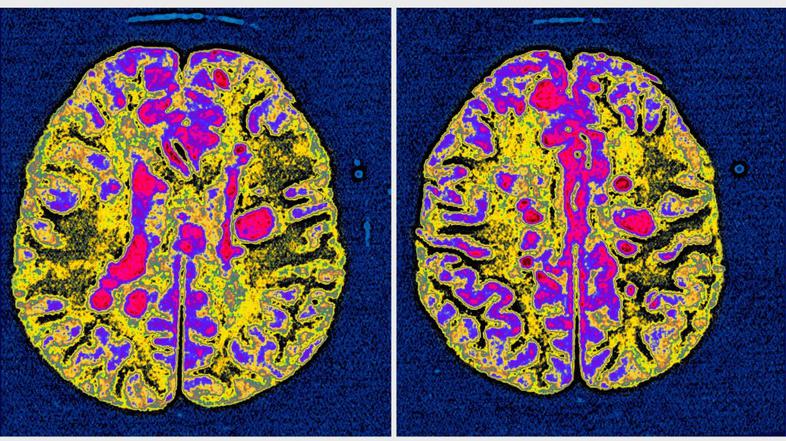

Prva zdravila so prišla na tržišče pred dobrimi 25 leti, vendar je bila dostopnost do njih slabša, saj so bolniki postali ustrezni kandidati za zdravljenje šele dokaj pozno v poteku bolezni. "Dandanes vemo, da bolezenski proces zajame celotne možgane in ga sestavljata tako vnetna kot nevrodegenerativna komponenta, ki je pridružena že zgodaj na začetku bolezni. Prav slednja je tista, ki vodi v nezadržen propad možganovine, ki se slikovno kaže kot zmanjšanje možganskega volumna (atrofija), bolniku pa prinaša pomembno funkcionalno oviranost," je še pojasnila nevrologinja. "Sodobni diagnostični kriteriji in razvoj slikovnih metod omogočajo izredno zgodnjo postavitev diagnoze in s tem pričetek zdravljenja. Enotne učinkovine za zdravljenje multiple skleroze ni, obstajajo zgolj zdravila, s katerimi umirjamo oziroma spreminjamo vnetni odziv v telesu/ možganih, le nekatera izmed njih pa delno vplivajo tudi na proces propada možganovine," je dodala .